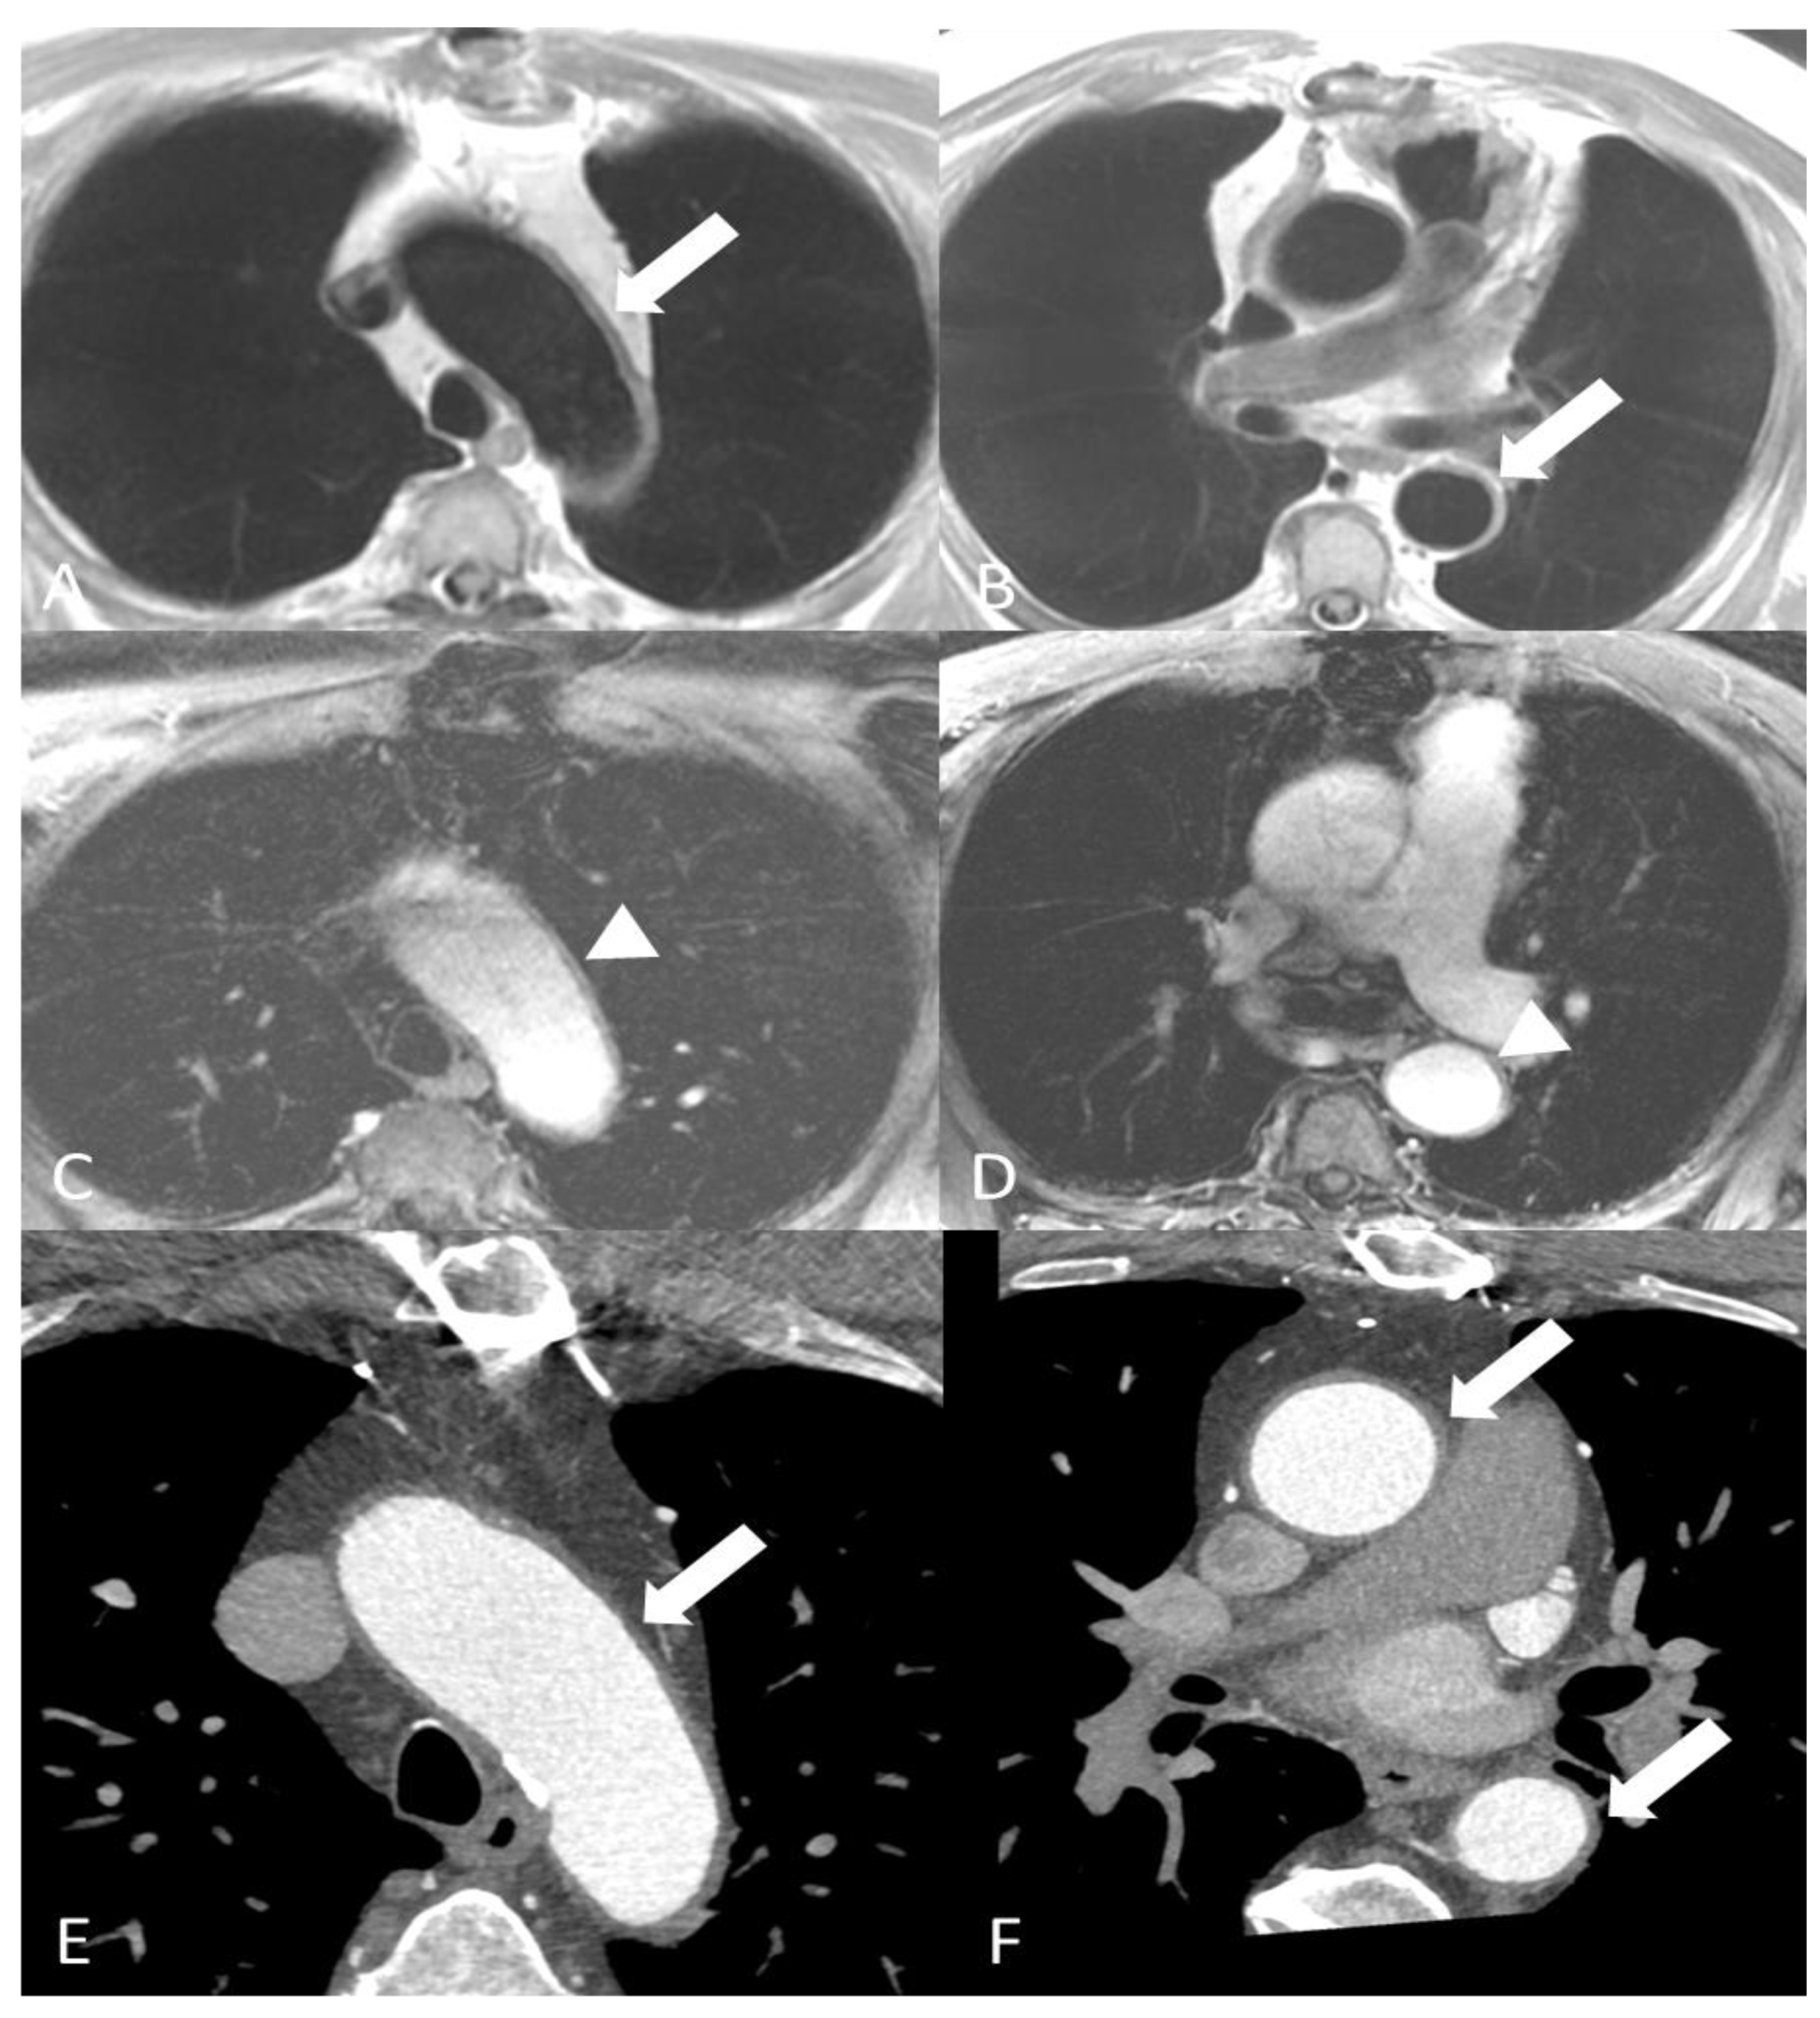

2.1.2. Takayasu’s Arteritis

2.1.3. Clinically Isolated Aortitis (Idiopathic Aortitis)